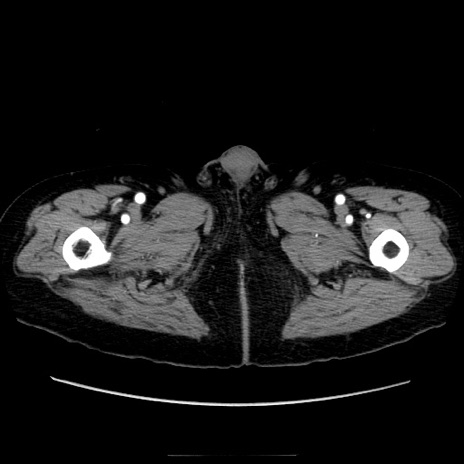

冠状断像

症例21(横断像)

【症例】70歳代男性

【現病歴】肝硬変・肝細胞癌にてかかりつけの方。約9時間前に食後より腹痛出現。症状が徐々に増悪し、嘔吐出現したため来院。

【既往歴】肝硬変、肝細胞癌(RFA、TACE後)